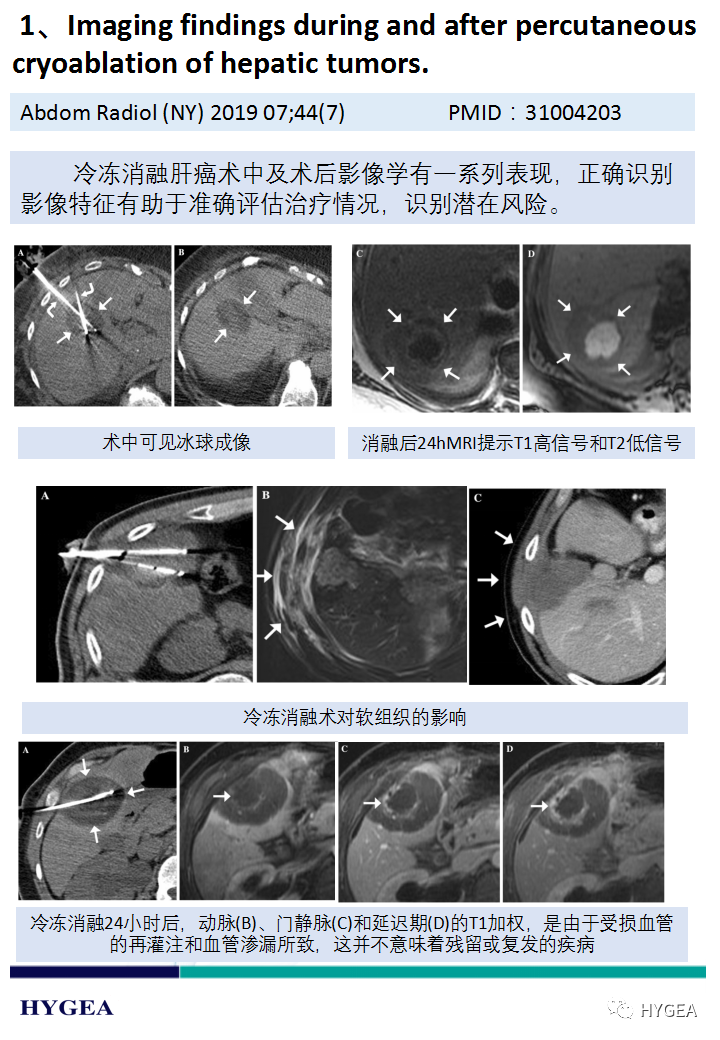

【海杰亚科研资讯】第187期——冷冻消融肝癌专题